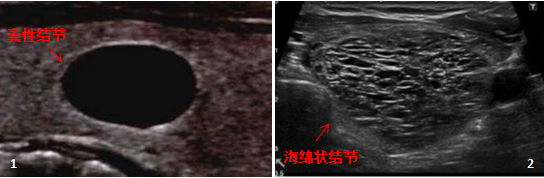

第二步:比较回声

以正常甲状腺组织回声为参考,结节回声可分为:无回声、低回声、等回声和高回声(图5~8)。 另外,结节的回声也有极低回声,可利用邻近的前颈。 肌肉回声用作参考(图 9)。

![图片[4]-一份甲状腺超声报告到手,从哪看起?-首码网-网上创业赚钱首码项目发布推广平台](https://mmbiz.qpic.cn/mmbiz_png/XsibUvKtQsKzC8FZ8sRv8kEBOSbCDCZwPLW7zW0WSibhrUXNpu4bX0R6fm5AsMuWR51BHYFgUNJj0DIkfibH6jpkA/640?wx_fmt.png)

资料来源:2017 ETA 指南《成人甲状腺结节超声恶性风险分层》

结节表现出低回声和非常低回声的情况,恶性风险增加,甲状腺乳头状腺癌更为常见。 滤泡性癌和滤泡性变异乳头状癌可为等回声或高回声。